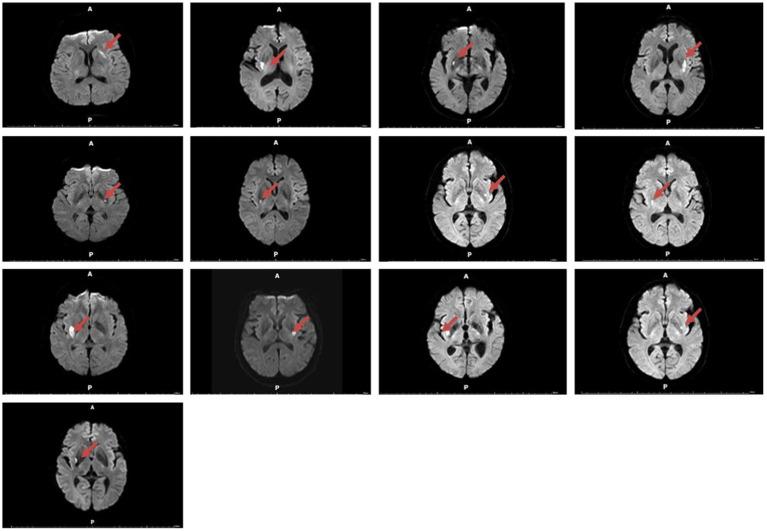

We collected data from patients of the First Affiliated Hospital of Xiamen University between August 2021 and August 2024. We screened some patients with dorsal striatum injury and asked a series of questions at the time points of 1 month, 3 months, 6 months, and 12 months after brain injury. Ultimately, 13 patients with dorsal lesions who met the inclusion criteria and a control group of 13 patients with brain injuries in other regions were selected.

We observed that patients with dorsal striatum damage experienced smoking cessation more readily and earlier compared to the control group. Furthermore, those with more severe dorsal striatum damage might maintain this cessation for longer. Additionally, nicotine dependence scores on the Fagerström Test for Nicotine Dependence (FTND) were lower in patients with dorsal striatum damage compared to the control group, indicating a reduced level of nicotine dependence.